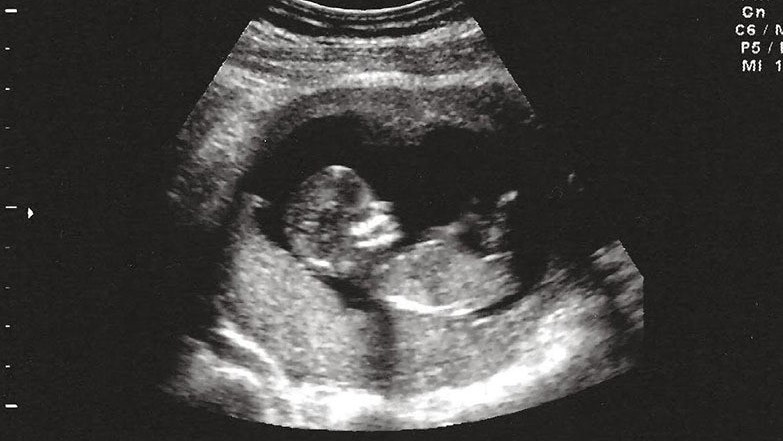

Mẹ bé, 38 tuổi, dự sinh ngày 20/3, tuy nhiên mang thai đến 24 tuần thì siêu âm phát hiện thai nhi thoát vị hoành, ngôi ngược. Chị vào Bệnh viện Sản Nh...